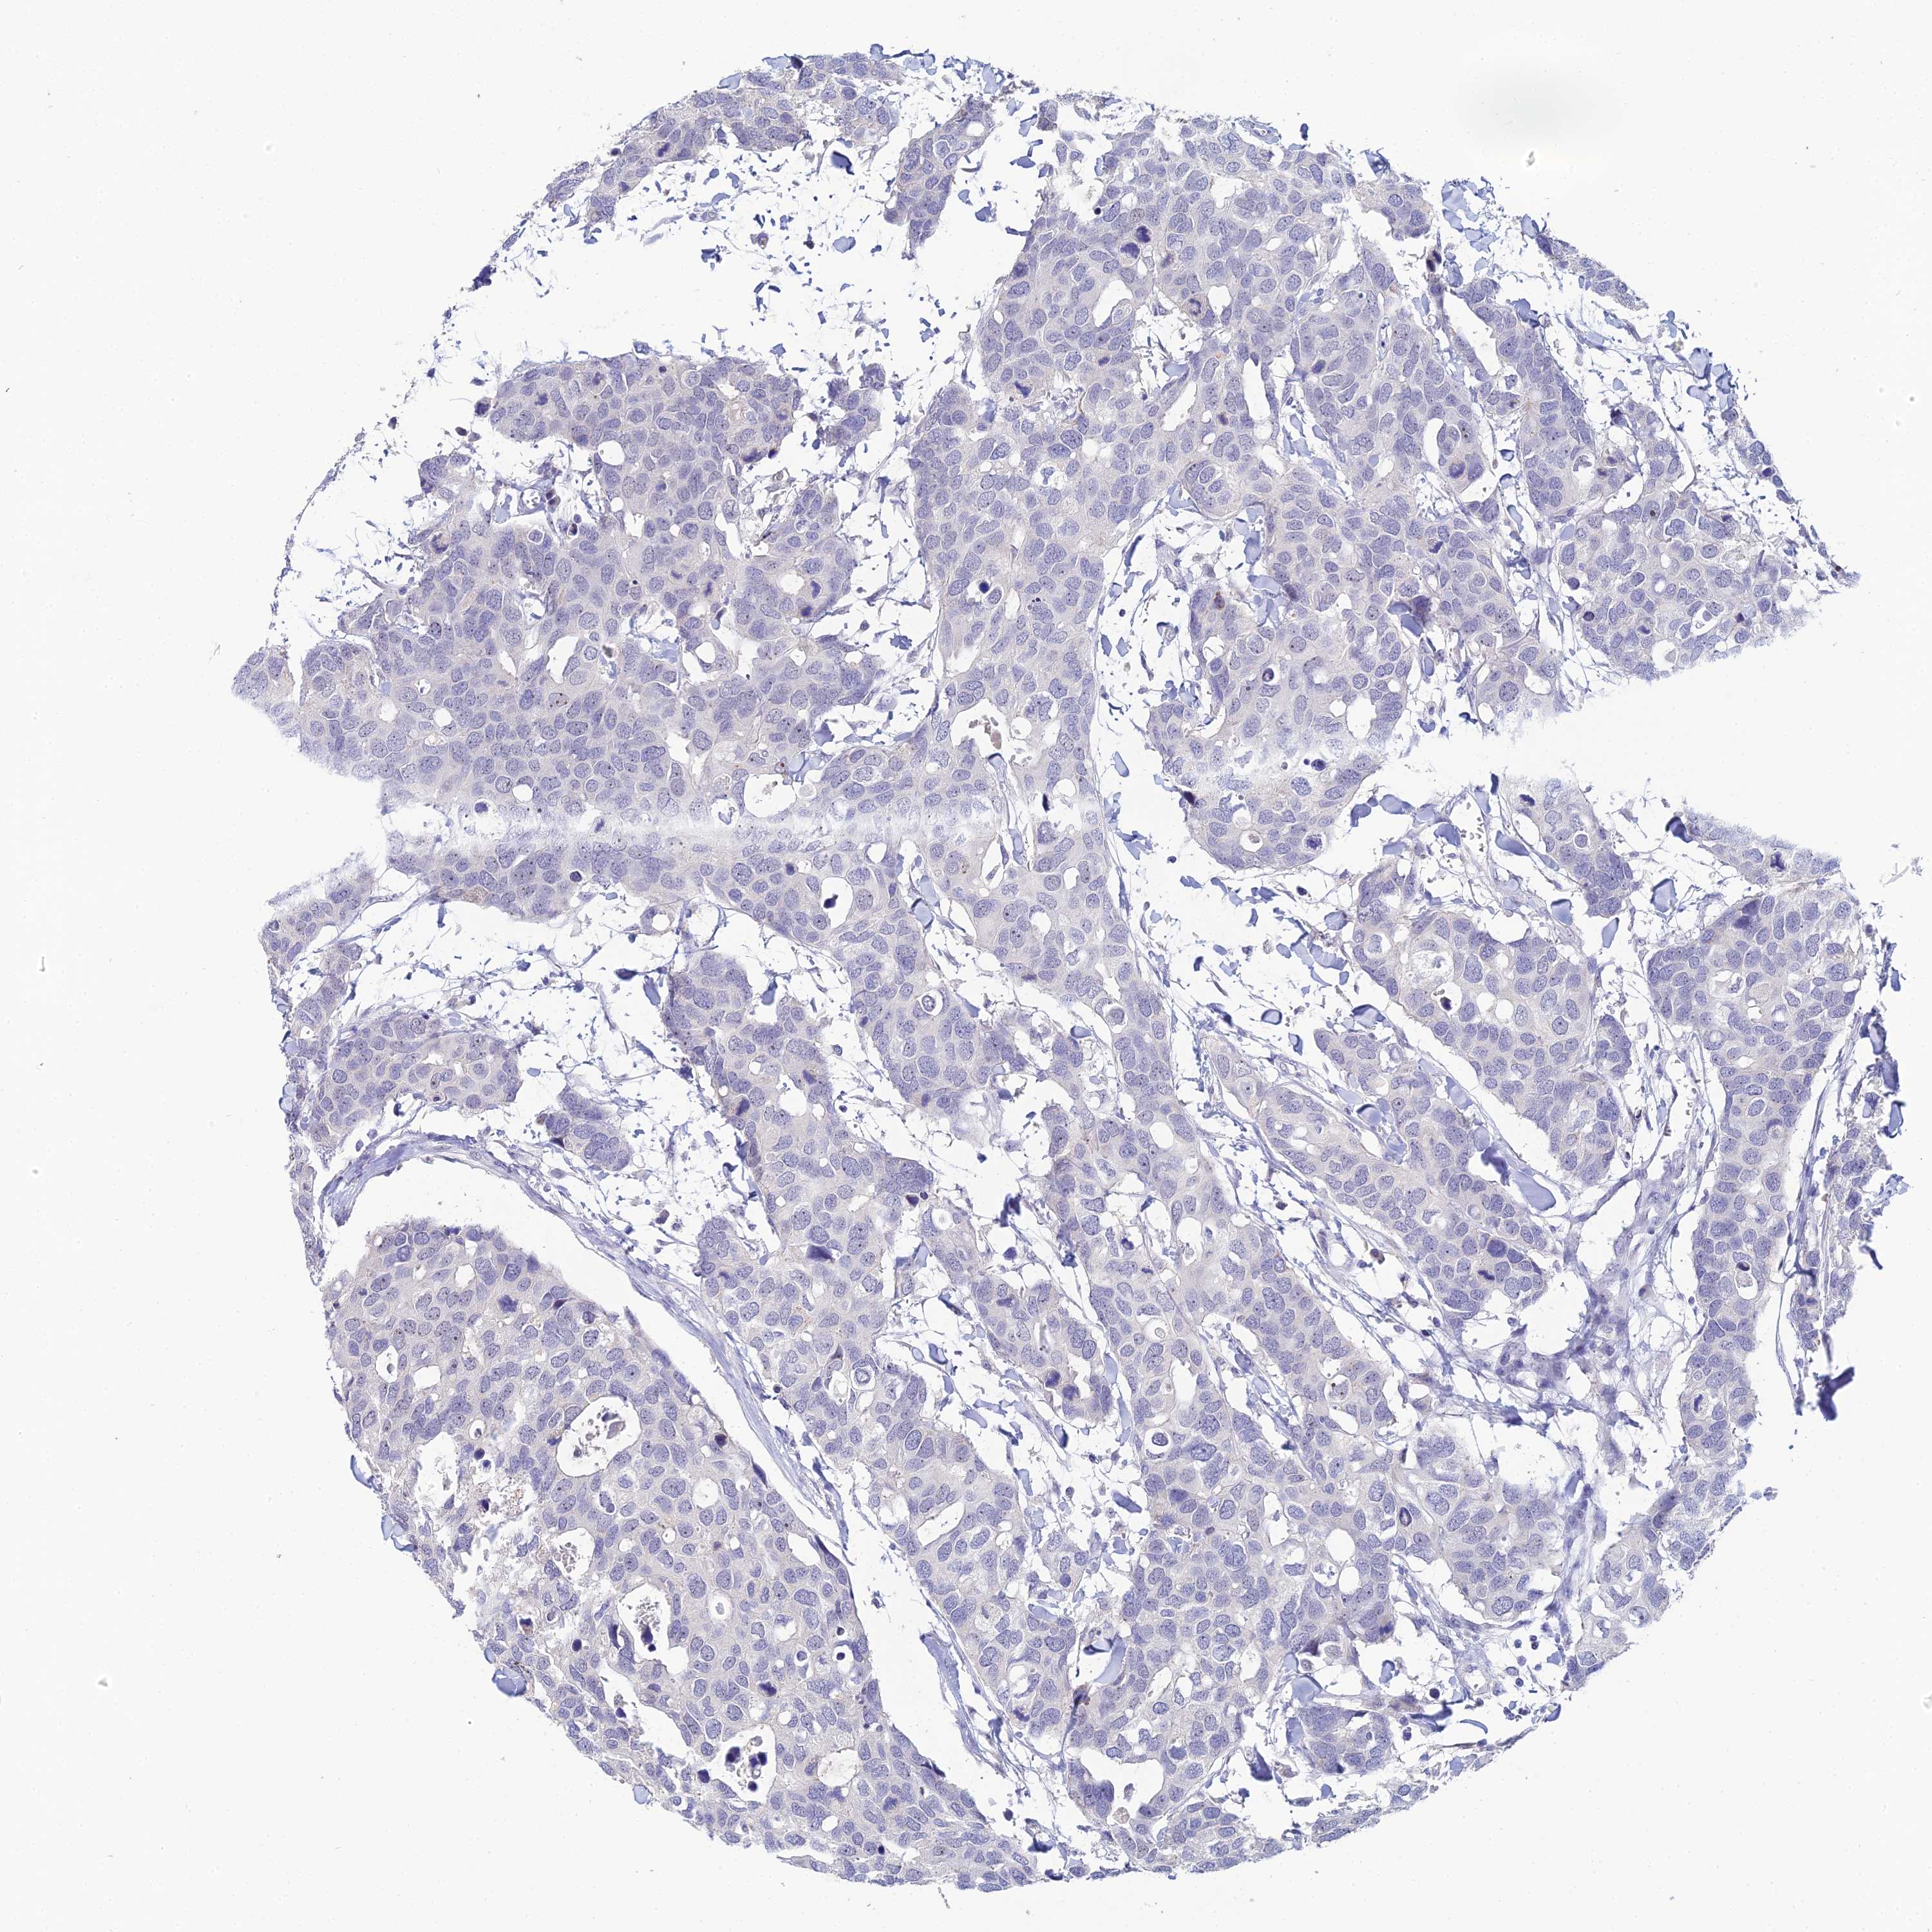

CANCER BREAST CANCER Show tissue menu

BRCA TCGA BRCA VALIDATION PROTEIN EXPRESSION

Breast cancer

Human cancer

Breast invasive carcinoma